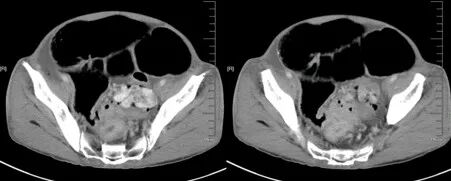

肠套叠

肠套叠是指一段肠管套入与其相连的肠腔内,并导致肠内容物通过障碍。肠套叠占肠梗阻的15%~20%。有原发性和继发性两类。原发性肠套叠多发生于婴幼儿,继发性肠套叠则多见于成人。绝大数肠套叠是近端肠管向远端肠管内套入,逆性套叠较罕见,不及总例数的10%。

降结肠癌并肠套叠